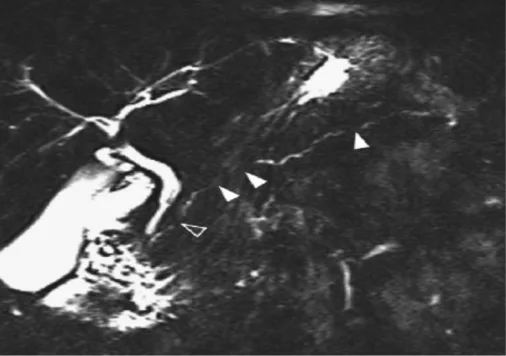

1) Typiques : c’est le rétrécissement, voir la disparition du CPP sur plus d’1/3 (> 5 cm de longueur) de la glande sans dilatation d’amont ou avec une dilatation modérée < 5 mm, ou bien des sténoses multiples sans dilatation d’amont. Les signes canalaires typiques sont retrouvés dans 40 à 50 % des cas (Fig. 9).

Figure 9. Aspect canalaire typique d’une PAI de type II sur une CP-IRM parfaitement techniquée. Critère 1D de la classification ICDC